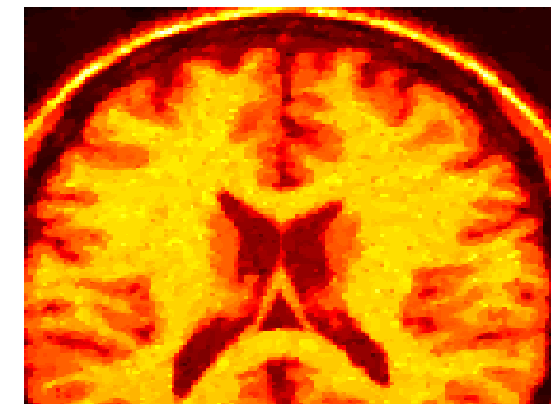

4.2 Magnetic resonance imaging

Gaussian noise images typically arise within the framework of magnetic resonance imaging (MRI). The challenge in this case consists in training the machines so that a clearer image is obtained. The magnetic resonance images seem to be the natural choice for our methodology, since a training set of images is often at hand.

For such a training set we consider the solution of problem (40). In Figure 2 the noisy images together with the final optimized ones for a brain scan are shown. For this experiments a mesh step size of was considered. The Tikhonov regularization parameter took the value , while the Huber regularization parameter was chosen as .

With this values, the optimal parameter value for the MRI image with 3% of noise was . When the noise in the image was of 9%, the computed optimal weight was .